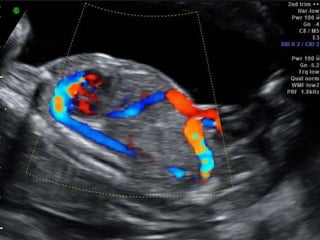

Ultrasound imaging and insonation

• A Sagittal anterior insonation offers the best

visualization of the Ductus venosus .

• An oblique transverse section may be more

convenient and easier to obtain in some fetal

position but rarely offers visualization of the

entire length of the vessel.

• Color Doppler is an indispensable tool to

identify the high velocity flow at the isthmus

of the ductus venosus.